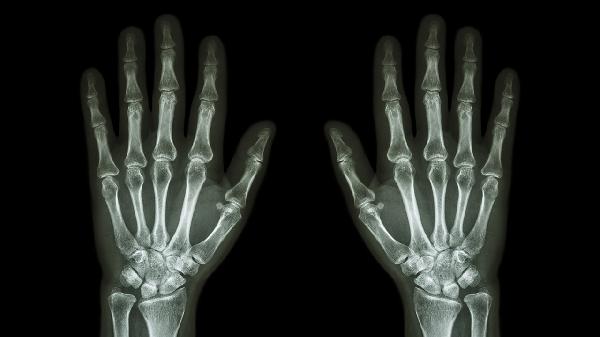

手指关节受到撞击、扭伤或过度使用可能导致局部软组织损伤或微小骨折。表现为关节肿胀、淤青和活动受限。可通过冰敷缓解肿胀,使用弹性绷带固定关节,必要时拍摄X线片排除骨折。若疼痛持续超过3天或伴有明显畸形,需骨科就诊。